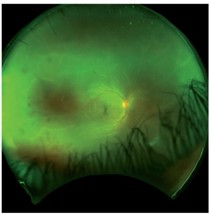

Vitritis is a feature of ARN and can vary from mild to severe. Dilated retinal examination may show patches of multifocal white infiltrates, most commonly in the retinal periphery. Initially, this may be subtle and these areas often evolve to become more confluent and sharply demarcated as necrosis develops. Lesions spread posteriorly without treatment and this can be a rapid process. Involvement of more than 25% of the retina is a poor prognostic sign (Fig 1)6.

Fig 1. Optos images of right (A) and left fundus (B) in a case of bilateral VZV acute retinal necrosis with vitritis, widespread multifocal retinitis, retinal haemorrhages and optic nerve swelling